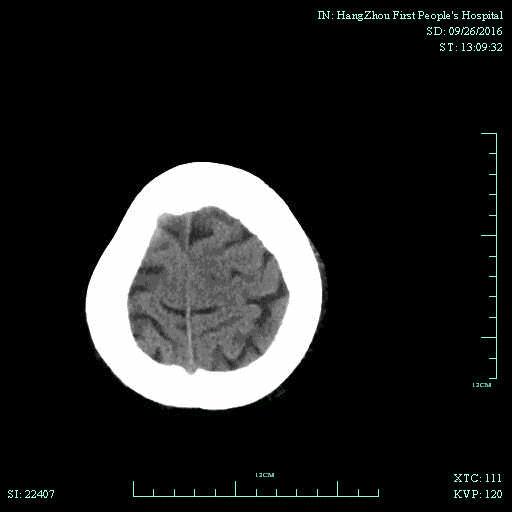

辅助检查:血常规、生化、凝血功能未见明显异常,心电图:心房颤动,ST-T改变;头颅CT平扫未见明显出血。

▼术前头颅CT平扫: